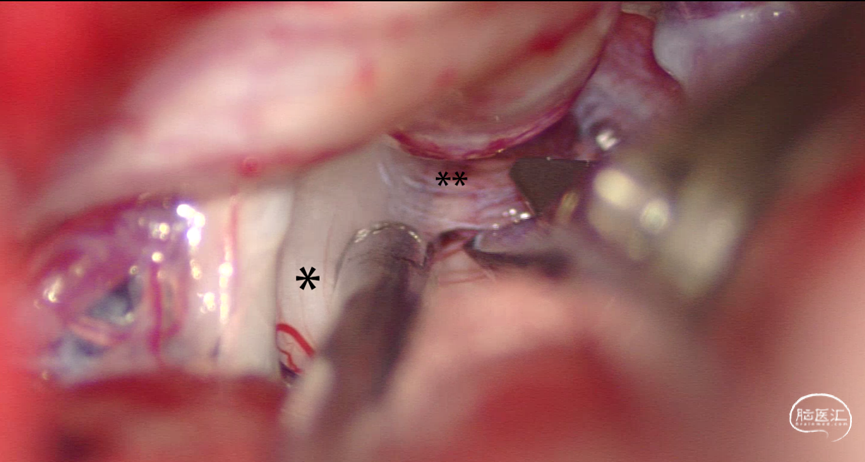

(1)手术观察:在手术过程中,我们发现7例患者(17.50%)存在静脉合并蛛网膜粘连(Arachnoid Adhesions, AA)压迫三叉神经,而33例患者(82.50%)则仅存在AA压迫。这一发现提示,AA可能是ATN的重要致病因素之一(图2)。

图2:在微血管减压术(MVD)中发现AA压迫了三叉神经。(*,三叉神经;**,蛛网膜)